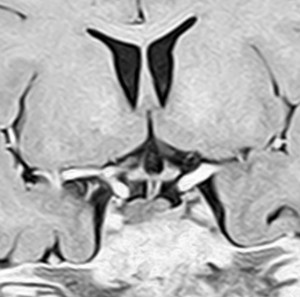

血清HCG-beta 4.5mIUで,下のMRIに見られるように第3脳室(視床下部)のグリオーマ(毛様細胞性星細胞腫)と見間違うような腫瘍でした。下垂体柄は太くなっていないし下垂体のサイズも普通です。もちろん水頭症もありませんので,開頭手術で生検をしてgerminomaの診断を得ました。

上のMRIで視神経交叉が腫大しているのが解りますが,下のMRI CISS画像では更に明らかです,左右の視神経と視交差と視索が腫大していました。視力を計ったら,右0.6,左1.5でいびつな視野欠損がありました。腫瘍はのう胞形成しながら左の視床下部から大脳基底核にも浸潤していました。